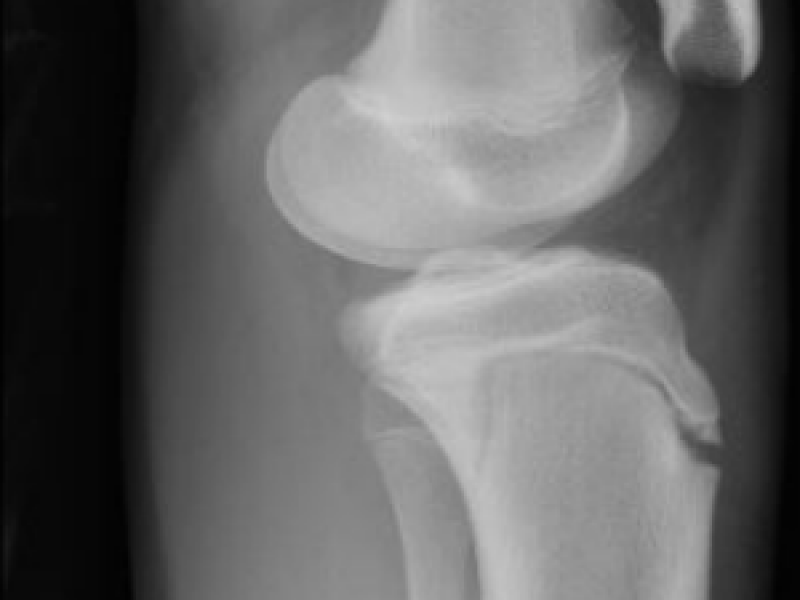

A 14 yo M presents to the ED complaining of L knee pain